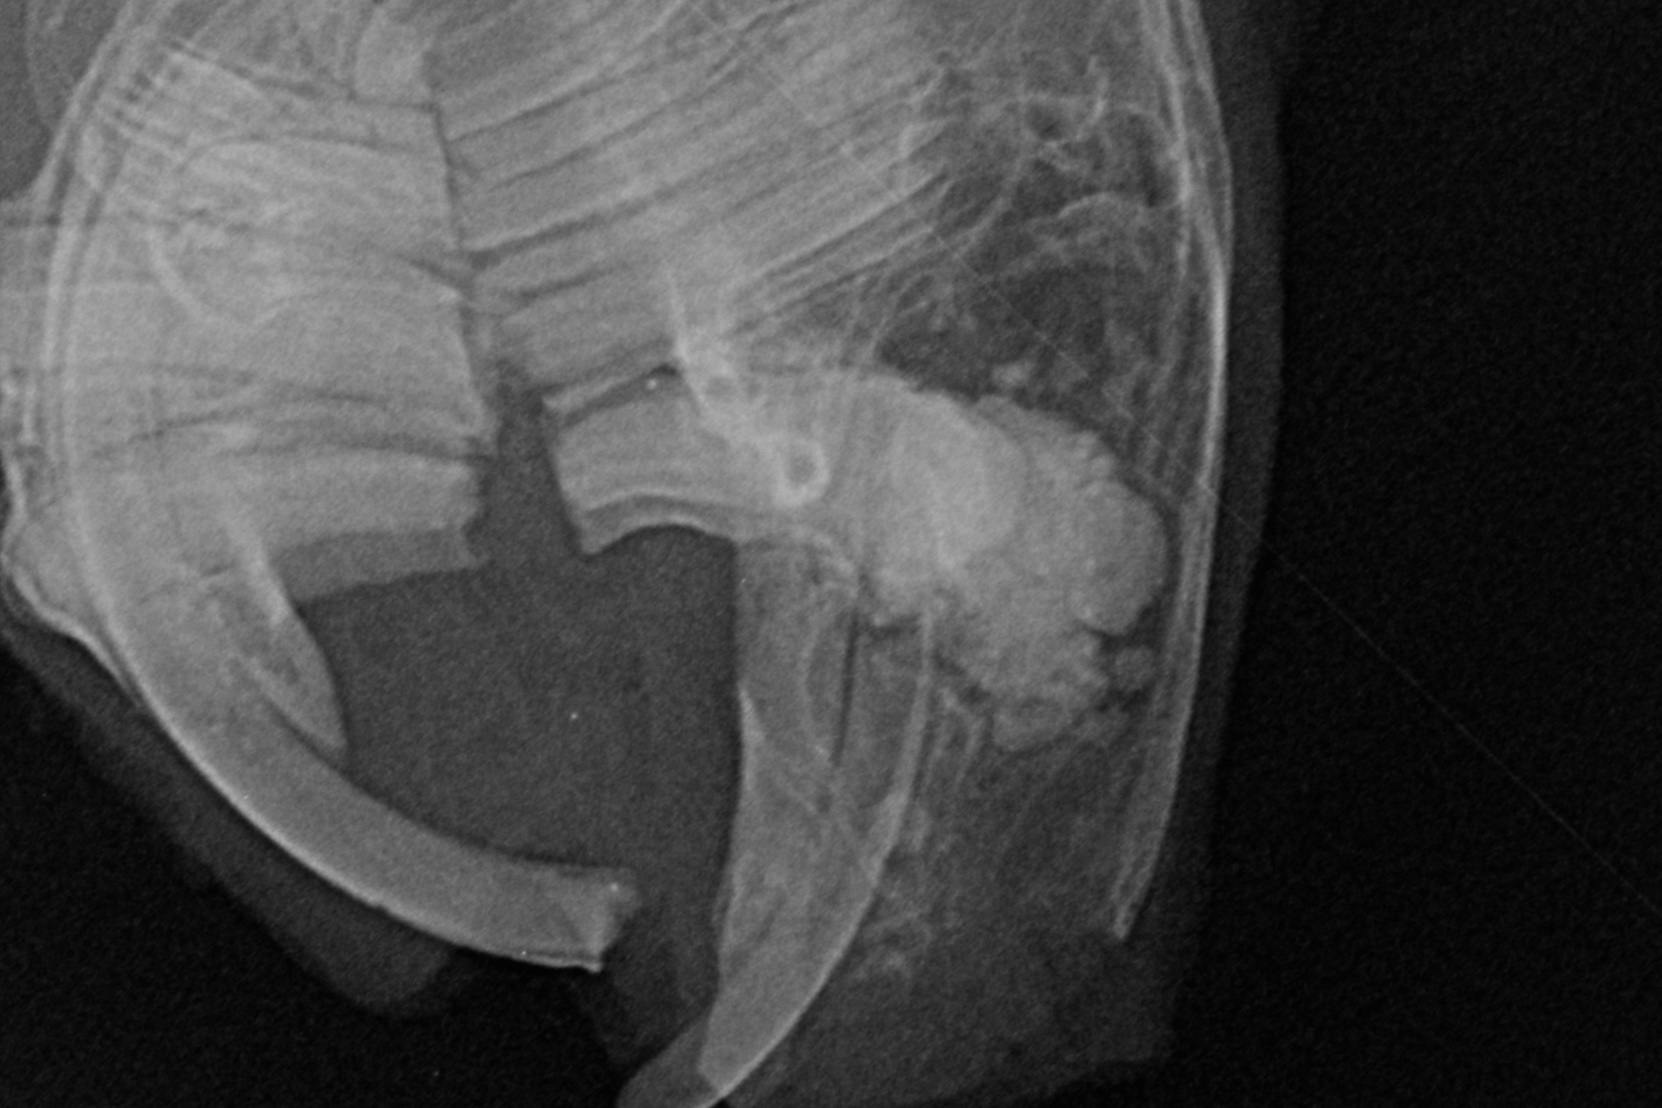

Ein paar Beispielaufnahmen

aus unserer Röntgenpraxis